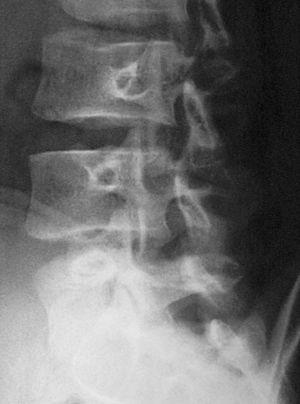

En la visita siguiente el paciente se presenta con radiografías que confirman el diagnóstico de espondilólisis L5 unilateral derecha (figs. 2 y 3). De acuerdo con el Documento de Consenso de la Societat Catalana de Medicina de l'Esport, se solicita una gammagrafía ósea planar (GOP) con tomografía computarizada por emisión de fotón simple (SPECT). Se decide continuar con el mismo tratamiento y se informa al paciente que será un tratamiento a largo plazo.

Figura 2

Figura 3